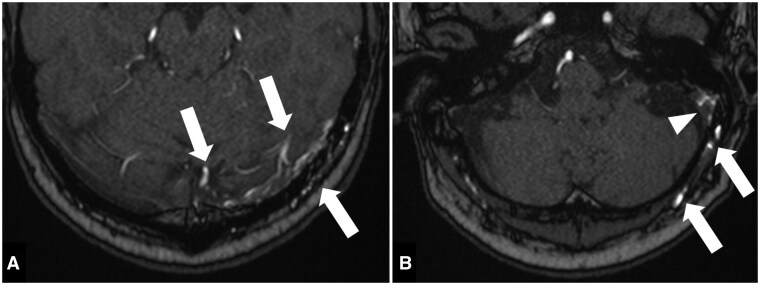

一名63岁男性表现为急性发作的间歇性头晕、视觉障碍和左颞头痛。检查发现左侧乙状窦有硬脑膜动静脉瘘(dAVF),分类为Cognard IIb型。使用线圈和Onyx进行成功的经静脉栓塞治疗,导致dAVF完全解决,没有立即并发症。然而,栓塞后3天,患者出现头痛、头晕、视觉不适和失读。MRI显示左侧颞枕区血管源性水肿,原因是静脉流出梗阻。尽管给予依诺肝素和地塞米松治疗,患者仍出现进行性症状,包括物体命名困难、记忆力下降和非惊厥性癫痫发作。随访影像显示水肿改善和稳定的最小局灶性胶质瘤。这例罕见的患者在硬脑膜AVF血管内栓塞后出现失读症,强调了术后监测的重要性,并提示预防性抗凝治疗可以降低可能的并发症风险。

A 63-year-old male presented with acute onset of intermittent dizziness, visual disturbances, and left temporal headache. Investigations revealed a dural arteriovenous fistula (dAVF) at the left sigmoid sinus, classified as Cognard type IIb. Successful therapeutic transvenous embolization was performed using coils and Onyx, resulting in complete resolution of the dAVF without immediate complications. However, 3 days post-embolization, the patient developed headache, dizziness, visual discomfort, and alexia. MRI findings suggested vasogenic oedema in the left temporo-occipital area due to venous outflow obstruction. Despite treatment with enoxaparin and dexamethasone, the patient experienced progressive symptoms including difficulty in object naming, memory decline, and nonconvulsive seizures. Follow-up imaging indicated improvement of oedema and stable minimal focal gliosis. This rare case of a patient developing alexia following endovascular embolization of a dural AVF highlights the importance of post-procedural monitoring and suggests potential benefits of prophylactic anticoagulation to reduce the risk of probable complications.